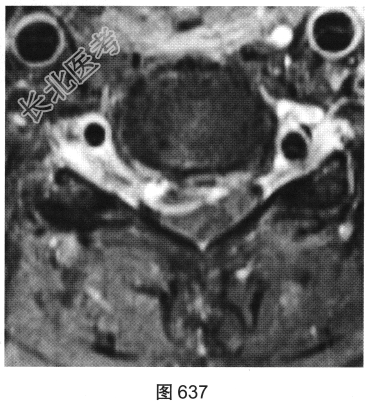

- [材料题] 患者女性,49岁,颈部胀痛伴双手麻木3天。MRI检查见图632~图637。

- 多项选择题1.患者MRI图片有哪些阳性征象( )

A、同水平硬膜囊及脊髓明显受压

B、病变与硬膜夹角为钝角

C、病变呈环形强化,中心未见明显强化

D、病变在髓外硬膜下

E、病变跨越右侧椎间孔,呈哑铃状改变

F、C

水平硬膜外梭形软组织信号